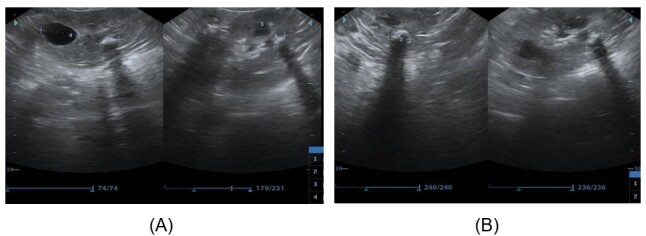

Abstract Image